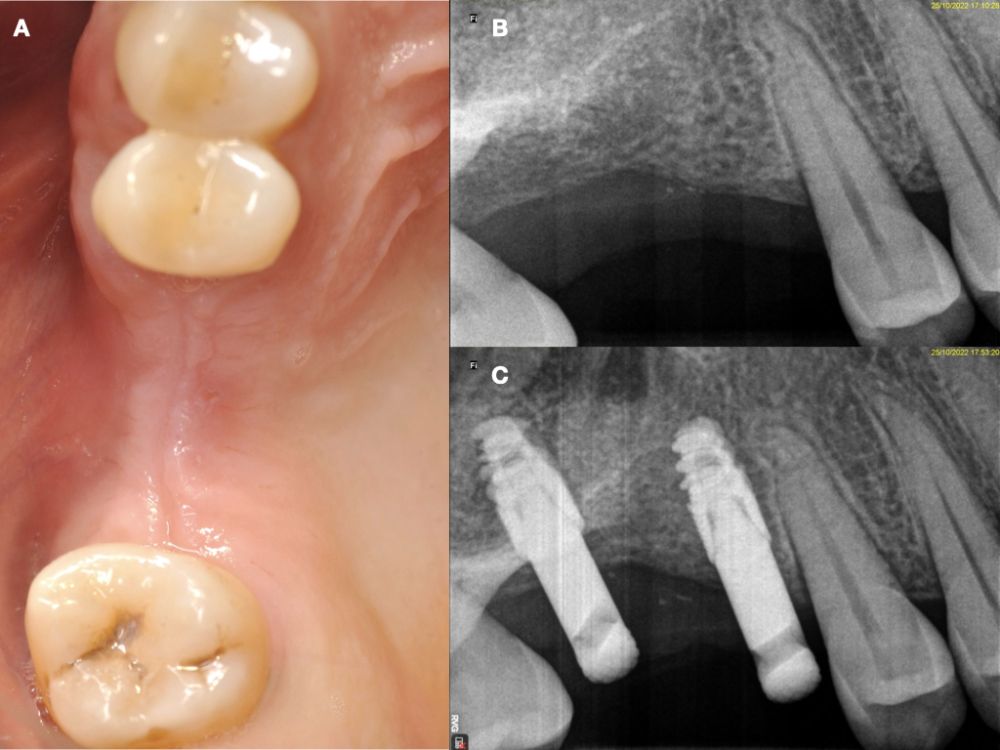

Seis meses tras la cirugía de elevación de seno maxilar se realizó la reentrada para la colocación de implantes. Se obtuvo una biopsia de tejido óseo de 3 x 7 mm mediante trefina y se solicitó un análisis histomorfométrico, obteniendo un 30,56% de hueso vital (Figura 7). Tras la muestra para la biopsia se colocaron dos implantes bone level Naturactis de ETK® (ETK Implants S.L, Sant Boi de Llobregat, España) con un torque de inserción de 35 Ncm, comprobándose su correcta colocación en el postoperatorio inmediato mediante una radiografía periapical (Figura 8). Seis meses tras la colocación de los implantes la paciente pudo acudir a realizarse la segunda fase para colocar pilares de cicatrización, y mediante un CBCT de comprobación se valoró la altura ósea final, teniendo un incremento de 4,2 mm en la zona del 1.6, y de 6,1 mm en la zona del 1.7 (Figura 9).

Quince días después de la segunda fase se realizó la toma de impresiones para la realización de dos coronas ferulizadas cemento-atornilladas sobre bases de titanio, comprobándose el ajuste mediante una radiografía periapical paralelizada (Figura 11). Seis meses tras la colocación de la restauración se realizó una revisión clínica y radiográfica, observando el buen aspecto de los tejidos blandos (Figura 12).